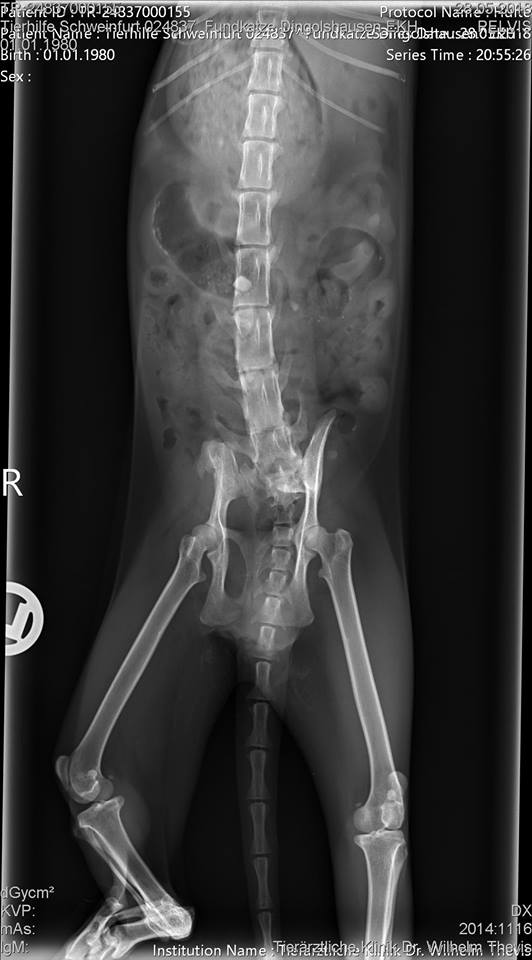

Dort stellte sich heraus, dass die Mieze tatsächlich einen Unfall hatte, jedoch schon vor einer Weile. Die Knochen sind jedoch leider alle krumm zusammen gewachsen, da sie wohl nie behandelt wurde :(. Nicht auszumalen, was die Süße an Schmerzen durchleiden musste. Außerdem fiel in der Tierklinik ihr schlechter Zustand auf: Sie war abgemagert, litt unter flüssigem Durchfall und war voller Parasiten.